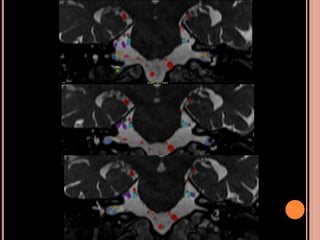

Achados de imagem NF2

 Schwannomas vestibulares (realce homogêneo

pelo contraste, seria hipo em T1)

 Meningeomas (realce intenso pelo contraste)

 Calcificação assimétrica de plexo corióide

SCWHANNOMAS

Pequenas lesões no CAI, bem mais caracterizada

nas aquisições volumétricas(3D CISS);

Aspecto de “sorvete de casquinha” quando lesões

maiores com extensão pontocerebelar;

Hipo em T1 e hiper heterogêneo em T2;

Impregnação pelo Gd homogênea se pequenos e

heterogênea se grandes;